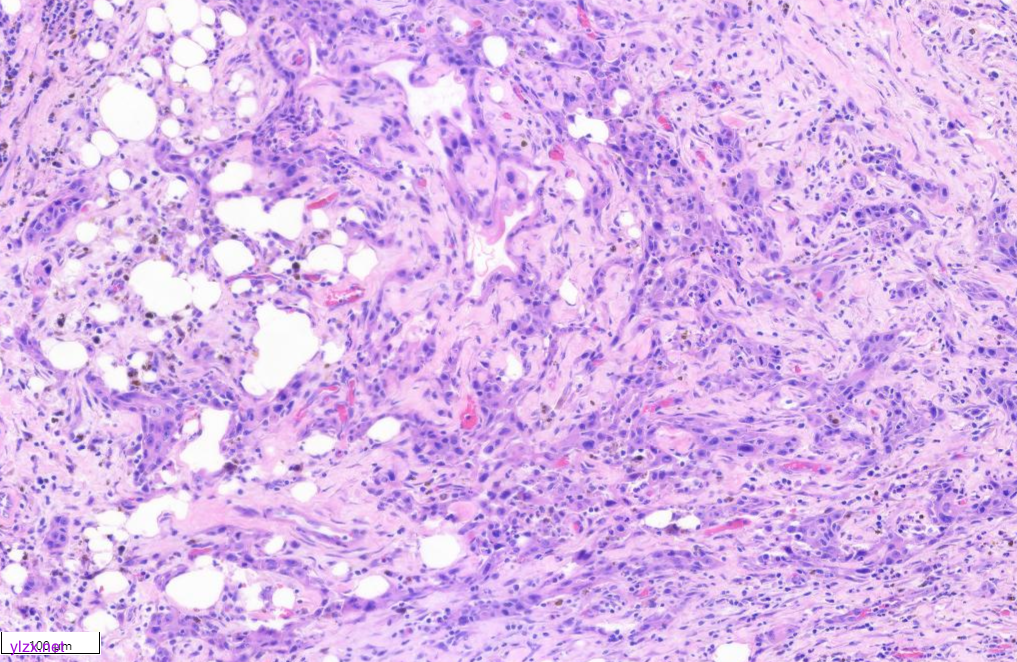

低倍镜下甲状腺乳头状癌区域与间变性癌鳞状细胞样亚型区域分界清,(图1)。低倍镜下,可见甲状腺乳头状癌呈乳头状、片状、索状分布,间质硬化(图2)。20倍镜,肿瘤细胞排列呈“铁轨”样,细胞立方形,细胞质丰富,淡嗜酸,细胞核圆,大小一致,染色质粗,核位于基底,可见小核仁,核内假包含体(图3)。鳞癌样区域(HEx10)肿瘤细胞呈多边形,梭形、上皮样,胞浆嗜酸,可见不全角化,肿瘤细胞间见脂褐素,肿瘤细胞侵袭性强,浸润至周围脂肪组织(图4、图5)。

图5 显示肿瘤浸润至周围脂肪组织